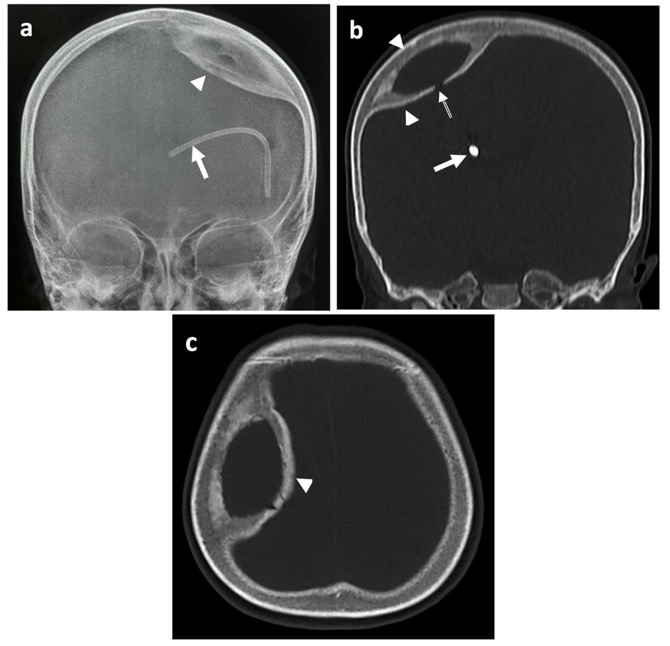

CT: lésion kystique intradiploïque bien définie

+ expansion de l'os pariétal droit